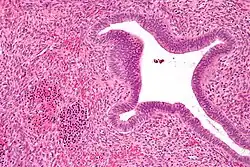

Micrograph showing nucleated red blood cells (bottom left of image), one of the elements necessary to call extramedullary hematopoiesis, in an endometrial polyp. H&E stain.